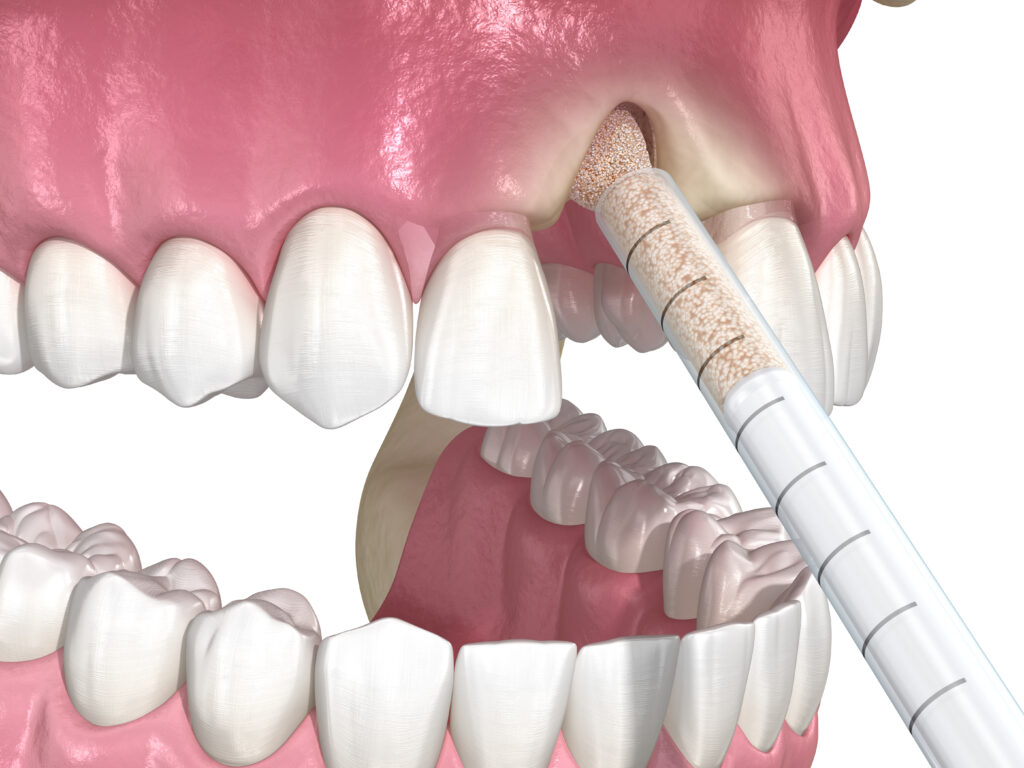

Sinus-lift

Sinus lift in dentistry is a surgical procedure aimed at restoring bone volume in the upper jaw. It becomes necessary…

Learn more

Step 3 — Treatment

The surgery is performed using state-of-the-art equipment. Our focus is on precision and minimizing trauma, whether it is one tooth extraction or a complex sinus lift.